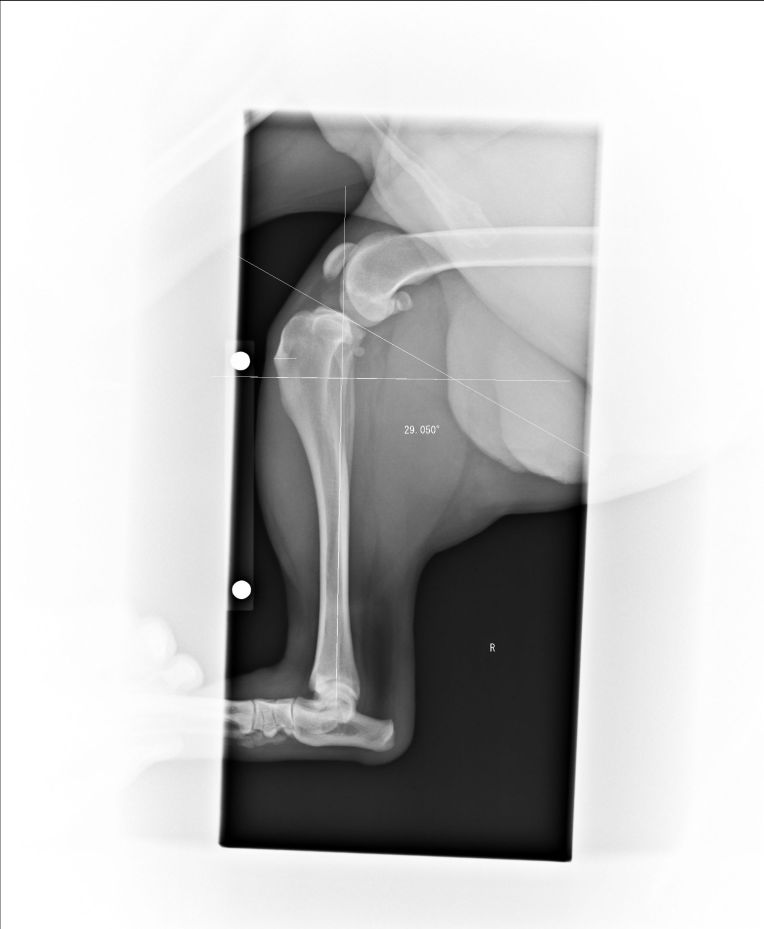

ERでは最初、診察室での問診から始まりましたが、いちくんが歩いている姿だけで、前十字靭帯は完全断裂していると即判断されました。

その後、再びのレントゲン検査、

血液検査、CT検査が行われました。

手術は、脛骨を切る角度の計算とか、とても難しいと聞いていたのと、